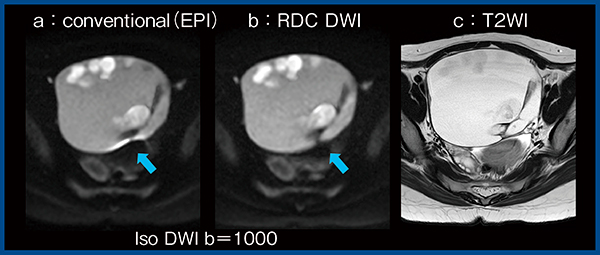

2.RDC DWI

“RDC(Reverse encoding Distortion Correction) DWI”は,EPIシーケンスにおいて,位相エンコード方向の反転により画像歪みの方向も反転することを利用して,位相エンコード方向の画像歪みを低減させる技術である。両方向のデータを収集し,それぞれの画像を補正後に加算した画像を出力することで,拡散強調画像(DWI)の歪みが低減される。

図6は卵巣成熟奇形腫の症例であるが,従来のDWI(a)で見られる磁化率アーチファクトがRDC DWI(b)では消えており(↑),よりT2強調画像(c)に類似した像を呈している。

磁化率アーチファクトを低減することで,腫瘍辺縁の拡散低下を示す壁在結節や微小な腫瘍の検出,播種結節などの偽病変との鑑別,腫瘍の進行期の評価などに有用な可能性がある。また,信号ムラが軽減されることで,背景の解剖学的構造の描出がより鮮明かつ均一となる。なお,子宮がんの症例において,従来のDWIとRDC DWIのADCマップを比較したところ,ADC値に大きな違いは認めなかった。

図6 RDC DWIと従来法の比較(卵巣成熟奇形腫)